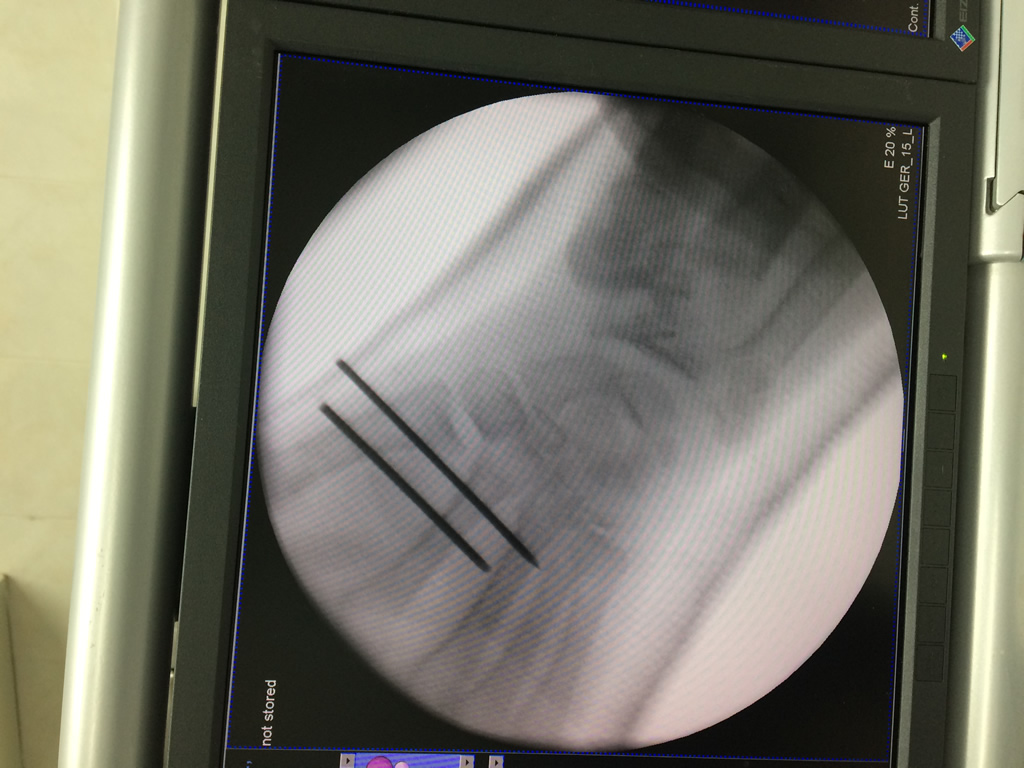

Cirugías de Codos - Cirugías de Muñecas y Manos

Los procedimientos más comunes en cirugía de la mano son aquellos destinados a reparar traumatismos, incluyendo lesiones de tendones, nervios, vasos sanguíneos, y articulaciones; huesos fracturados; y quemaduras, cortes, y otros daños de la piel.